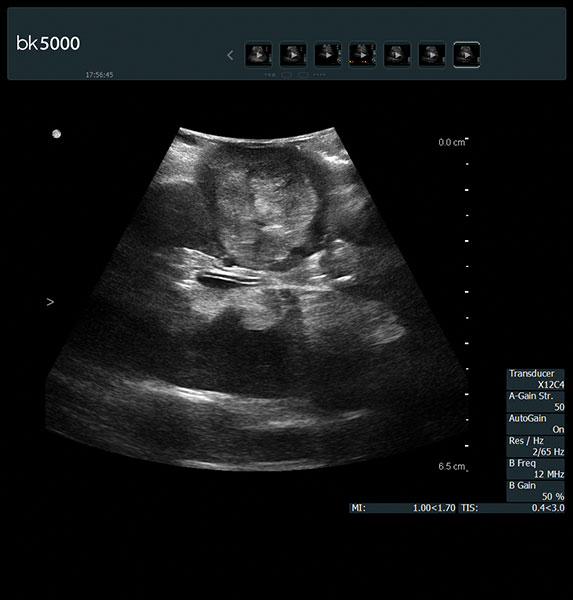

The unique Drop-In transducer enables access and visualization of complex organs and difficult-to-access anatomy in real-time. For example, in kidney navigation and difficult-to-access endophytic and exophytic tumors, the small, compact, curved linear array Drop-In transducer enables a wider field of view for faster examinations. The specially-designed fin grasped by the robotic arm ensures maximum control and organ contact so you can get the information you need.